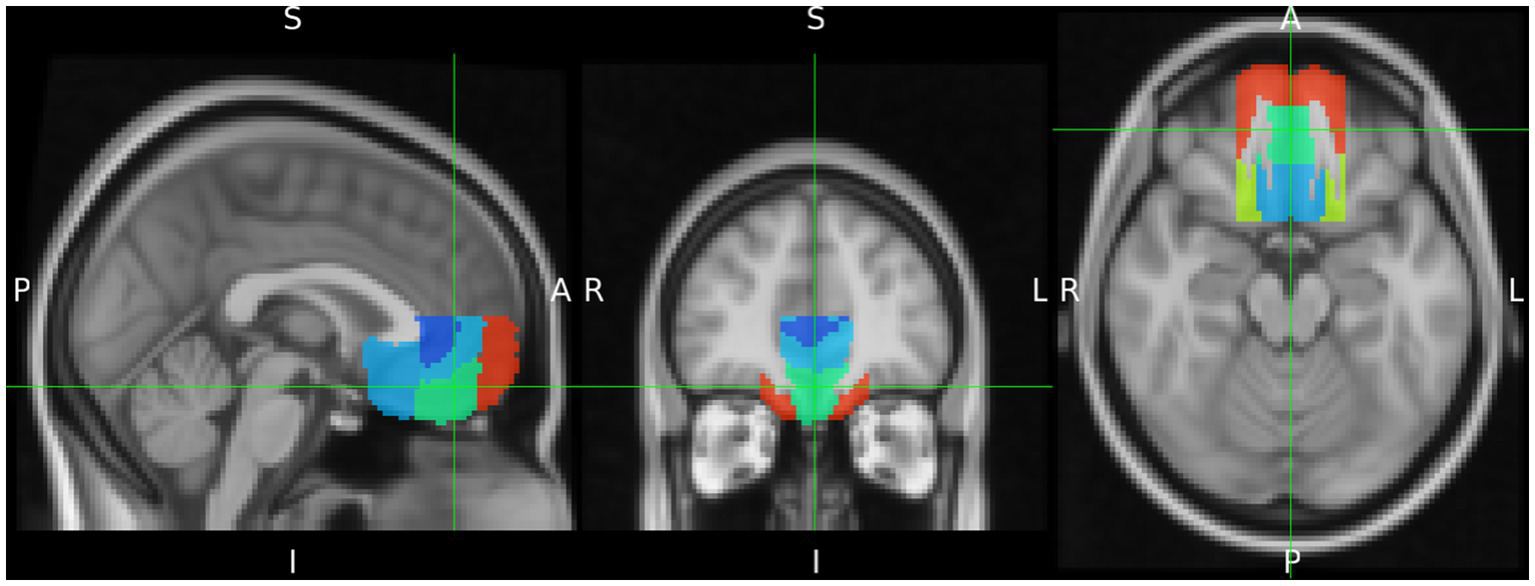

Since the definition of the vMPFC varies to some extent between different authors, anatomical VOI masks were defined according to the Harvard-Oxford Cortical Atlas (Desikan et al., 2006). In addition, in order to ensure comparability with other studies, the analysis of the vMPFC was calculated in terms of the regions defined by this atlas (Figure 2). To this end, the vMPFC was defined to include the ventral medial frontal pole, frontal medial cortex (FMC), ventral paracingulate gyrus, ventral anterior cingulate gyrus, and the subcallosal cortex, limited dorsally by the plane z = +10, and laterally by the planes x = ±20 (MNI152 coordinates) (Santos et al., 2011).

Figure 2

Delineation of the ventromedial prefrontal cortex (vMPFC) composed by regions of the Harvard Oxford Cortical Structures Atlas. It is projected on the MNI iso 2 mm brain. The green cross indicates the Frontal Medial Cortex as part of vMPFC.